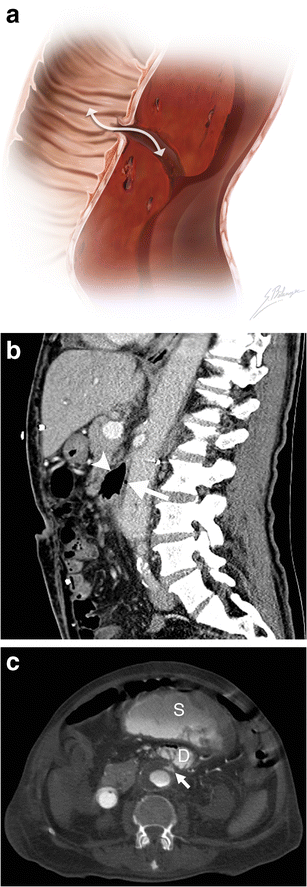

Aortoenteric fistula. a Illustration depicts a fistulous tract connecting a bowel loop to an aortic aneurysm. The white double-headed arrow shows communication between the structures allowing bowel gas to infiltrate into the aortic wall and blood to leak into the bowel lumen. b Sagittal enhanced CT image of a 73-year-old man demonstrates an aortoenteric fistula. Intraluminal gas (white arrow) is observed within the AAA, and normal fat planes between the aneurysm and the third portion of the duodenum are lost (white arrowhead). c Axial enhanced CT of an 82-year-old man who presented with massive lower gastrointestinal bleeding and a history of previously repaired AAA. Active contrast extravasation (white arrow) into the third portion of the duodenum (D) and the stomach (S) can be seen in this patient with an aortoenteric fistula